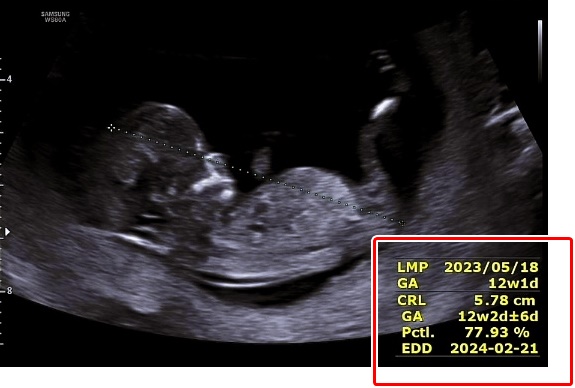

1. LMP (Last Menstrual Period): 최종월경일

마지막 생리 시작일을 의미합니다.

2. GA (Gestational Age): 임신기간, 임신주수

태아의 주수를 뜻하며 Ow Od (O week, O day), 주와 일수로 표기됩니다.

임신 몇 주 며칠인지 알 수 있어요.

3. EDD (Estimated Due Date): 분만 예정일

GA를 바탕으로 산정된 분만 예정일입니다.

EDC (Estimated Day of Confinement)라고도 하며 출산 예정일을 말합니다.

4. CRL (Crown Rump Length): 머리부터 엉덩이까지 길이

임신 초기에는 CRL로 태아의 크기(키)를 확인합니다.

임신 중기부터는 머리직경, 복부둘레 등으로 예상 키를 확인하기 때문에 중기부터는 크게 의미를 두지 않는다고 합니다.